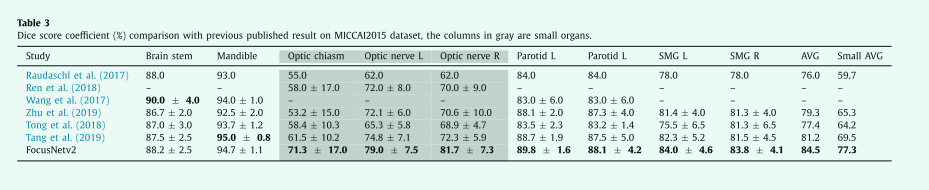

Processing time

深度学习方法的处理时间如表4所示,所有方法都使用相同的计算平台和NVIDIA TITAN Xp GPU进行测量。我们的骨干网络S-Net平均需要3.33秒来处理一次CT扫描。在添加SOL-Net和SOS-Net后,我们的Focus usNetv2需要4.36秒,仍然比DeepLabv3+快,但分割精度要高得多。我们的方法比AnatomyNet消耗更多的计算资源,但比DeepLabv3+少。考虑到放射治疗计划通常需要几个小时,并且不是一个时间敏感的任务,我们的方法可以在合理的时间内实现最佳性能。

表4在NVIDIA TITAN Xp GPU上进行一次ct扫描时,不同深度学习模型的平均推理时间